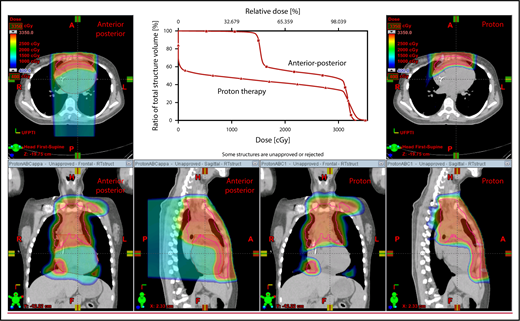

The take-off of the left main stem coronary artery is used to define whether the target is above or below the heart (Figure 2A). In this example (Figure 2B), the exposure of the heart is quite comparable, regardless of which technique is used. Differences in DVHs, as well as the mean dose to other structures, are similar to the proton and IMRT plans.

Three scenarios of the relation between mediastinal disease and the heart. (A) Showing how to use the takeoff of the left main stem coronary artery (outlined in pink) to determine the upper and lower mediastinal locations. (B) Scenario 1: coronal CT images of a 28-year-old man with primary mediastinal lymphoma before (i) and after (ii) 6 cycles of rituximab, cyclophosphamide, doxorubicin, vincristine, prednisone (RCHOP) chemotherapy presenting for consolidation with radiation. (Biii) Axial, coronal, and sagittal views of an IMRT plan (upper panels) and a proton plan (lower panels). (Biv) Corresponding mean doses to critical structures using IMRT vs protons. (C) Scenario 2: coronal CT images of a 25-year-old man with Hodgkin lymphoma before (i) and after (ii) 4 cycles of doxorubicin, bleomycin, vinblastine, and dacarbazine (ABVD) chemotherapy presenting for consolidation with radiation. (Ciii) Axial, coronal, and sagittal views of an IMRT plan (upper panels) and a proton plan (lower panels). (Civ) Corresponding mean doses to critical structures using IMRT vs protons. (D) Scenario 3: coronal CT images of a 30-year-old man with recurrent Hodgkin lymphoma as shown in the coronal images of a PET/CT scan (i-ii) presenting for definitive radiation. (Diii) Axial, coronal, and sagittal views of an IMRT plan (upper panels) and a proton plan (lower panels). (Div) Corresponding mean doses to critical structures using IMRT vs protons.

Scenario 2: target spans the right side of the heart

For the targets on the right side of the heart, IMRT often provide comparable doses to the heart and other structures as proton therapy. Notably, however, even when proton plans give a dosimetric advantage over IMRT plans, the magnitude of advantage could vary between cases, and it needs to be judged individually. For example, for the patient shown in Figure 2C, the mean doses to critical structures from proton therapy are sufficiently lower than those from IMRT to suggest that proton therapy may be preferred because of the large volume spanning the right side of the heart. This example illustrates the need for careful consideration of individual cases before deciding on treatment.

Scenario 3: target is on both sides of the heart

Disease that spans significantly in front of the heart anteriorly, posteriorly, or to the left side poses a particular challenge for IMRT; therefore, proton therapy may be the superior plan. Notably, toxicity to the heart and lungs is not eliminated by using proton therapy; rather, the dose to the heart may be lower than IMRT. Thus, for cases like in Figure 2D, clinicians should carefully weigh the therapeutic benefit against the long-term risks for radiation-induced treatment toxicities before deciding on which technique should be used. Indeed, in this case, proton therapy can significantly avoid the heart and should be sought in an attempt to reduce the dose to the heart substructures.